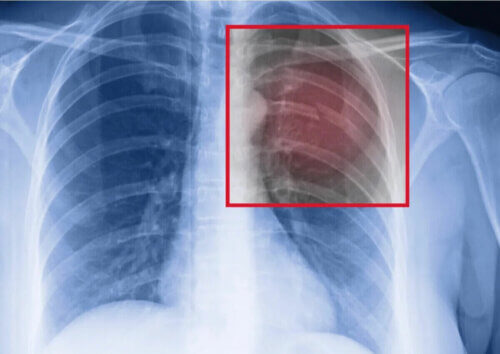

Si vous êtes un athlète et que vous souffrez d’une fracture de stress aux côtes, la première chose à faire est de consulter un médecin. Vous aurez une radiographie pulmonaire pour confirmer la blessure et son étendue sera évaluée.